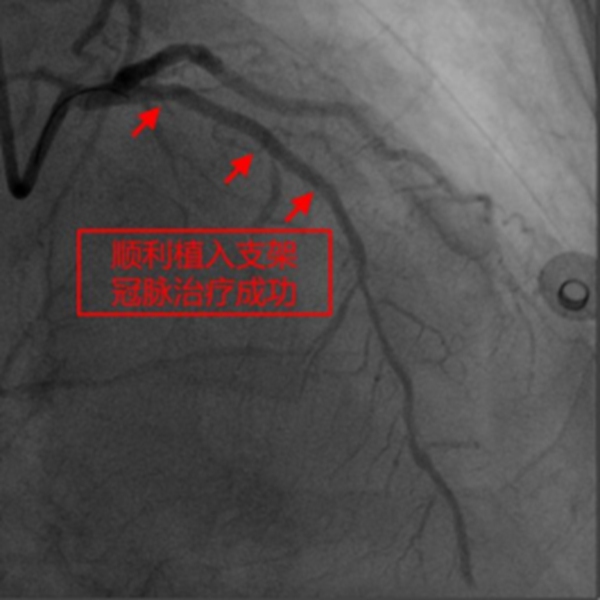

在征得患者及家屬同意,做好充分術前準備的情況下,冠脈介入團隊在冉擘力主任帶領下,按計劃給患者實施了血管內超聲(IVUS)指導下經皮冠脈旋磨+Shockwave沖擊波球囊碎裂鈣化斑塊及支架植入術,術中團隊克服了一系列困難,最終安全順利地完成了全部介入手術過程,完全碎裂了環狀鈣化斑塊,效果非常滿意,歷時約1個多小時,手術成功,病人安返病房。術后患者胸悶、氣短明顯緩解,對治療效果十分滿意。

據了解,冠脈斑塊旋磨術聯合沖擊波球囊治療是目前臨床實踐中征服重度冠脈鈣化病變的優化組合技術,不僅可以提高手術成功率,減少圍手術期并發癥,而且還極有可能改善患者遠期獲益,值得在臨床上推廣應用。該技術的應用使得重慶市人民醫院成為全國率先開展該技術的醫院之一,也標志著重慶市人民醫院心內科冠脈介入診療水平處于全市前列并再上新臺階。(通訊員 張勤)